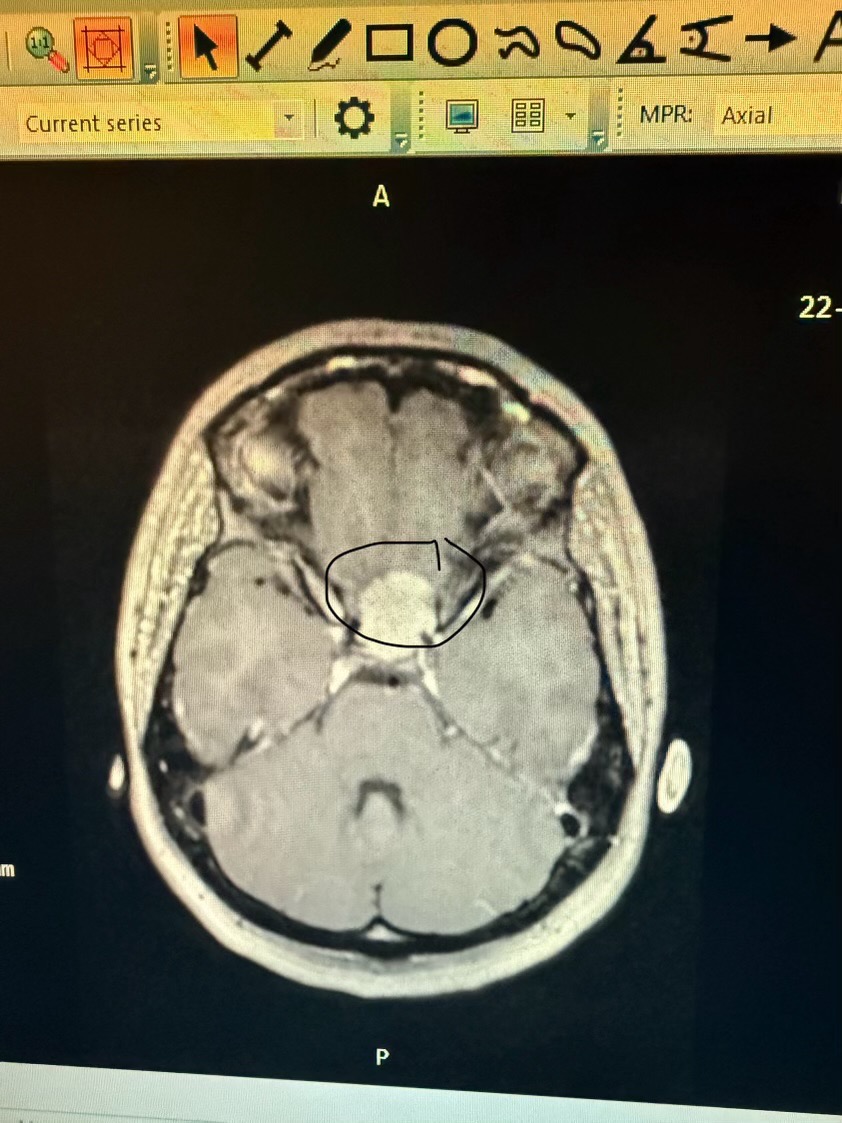

Help Support My Wife’s Fight Against a Brain Tumor

Our family’s world changed the day doctors told my wife she has a brain tumor. No one is ever ready for news like that — especially a mother of six beautiful daughters who adore her and need her more than anything.